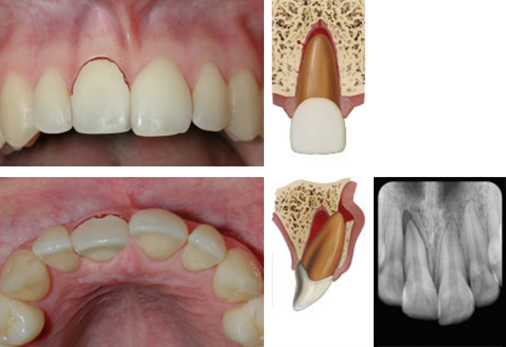

dx intrusion

A

Tooth displaced axially into alveolar bone

High metallic/ankylotic sound

Mobile

Negative sensibility tests

Occlusal, PA and 2 eccentric horizontal angulations

* PDL space may be absent from all or part of the root

* ACJ located more apically in the intruded tooth than in adjacent non-injured teeth, at times even apical to marginal bone level